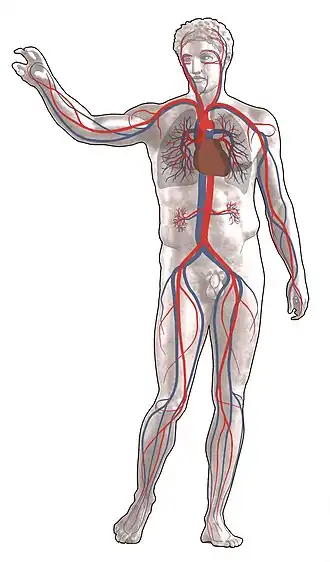

Aparatul cardiovascular (circulator) este un aparat care permite circulația sângelui și limfei în corp pentru a transporta nutrienți, oxigen, dioxid de carbon. Acest aparat este constituit din inimă și vasele de sânge (arterele, venele și capilarele) ce sunt răspândite într-o rețea deasă prin tot corpul.

Arterele reprezintă cele mai mari vase de sânge. Au rolul de a transporta sânge oxigenat de la inimă înspre țesuturi și organe.[4]

Pe desene sunt reprezentate cu culoarea roșie. Artera este compusă din trei straturi: tunica externă, tunica musculară (tunica mijlocie) și tunica internă.[1] Tunica externă e alcătuită din țesut conjunctiv cu fibre de colagen și elastină, de asemenea și fibre nervoase vegetative și vase de sânge ce asigură oxigen pentru peretele vascular. Tunica mijlocie, sau medie, e constituită din celule musculare netede și fibre conjunctive elastice. Tunica internă (numită și endoteliul vascular) e un epiteliu pavimentos simplu, aflat pe o membrană bazală și un strat subendotelial elastic.[5]

Venele sunt responsabile cu transportarea sângelui dezoxigenat din țesuturi, organe înapoi la inimă. Spre deosebire de artere, delimitarea între tunici nu e uniformă. Tunica internă de sub nivelul inimii prezintă valve în formă de cuib de rândunică, numite semilunare, care ghidează fluxul sanguin;[4] când sângele pornește în direcția bună, valvele rămân deschise datorită poziționării în formă de con. Dacă sângele vrea să o ia invers, ele se închid datorită presiunii. Acestea sunt prezente deoarece nu există nimic ce pompează sângele înapoi, deci el o poate lua în orice direcție. Tunica medie e mai subțire, pe când cea externă e mai groasă.[7]

Capilarele sunt cele mai mici vase de sânge, ajungând chiar și la un diametru de două sau trei celule (15-20 μm). Din cauza mărimii lor ele pot ajunge oriunde în corp. Cea mai deasă rețea de capilare se găsește pe alveolele pulmonare.

Capilarele rezultă din ramificarea metaarterelor, continuându-se cu venele capilare; au 0,5 mm lungime. Cu cât activitatea metabolică a țesutului e mai intensă, cu atât sunt prezente mai multe capilare.